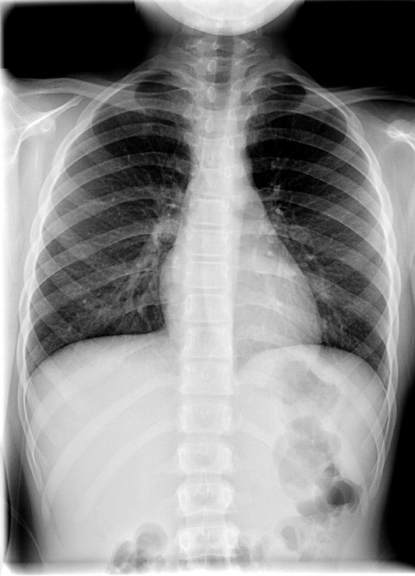

Identify the 1st thoracic vertebra and 1st rib. Click the image for labeling.